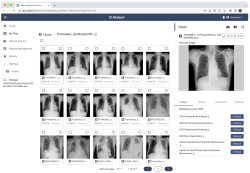

Promedius Inc. brings cutting-edge medical imaging AI cloud platform, AIdant to GITEX AFRICA 2023 (2)

(Source: GITEX Africa

2 years ago)